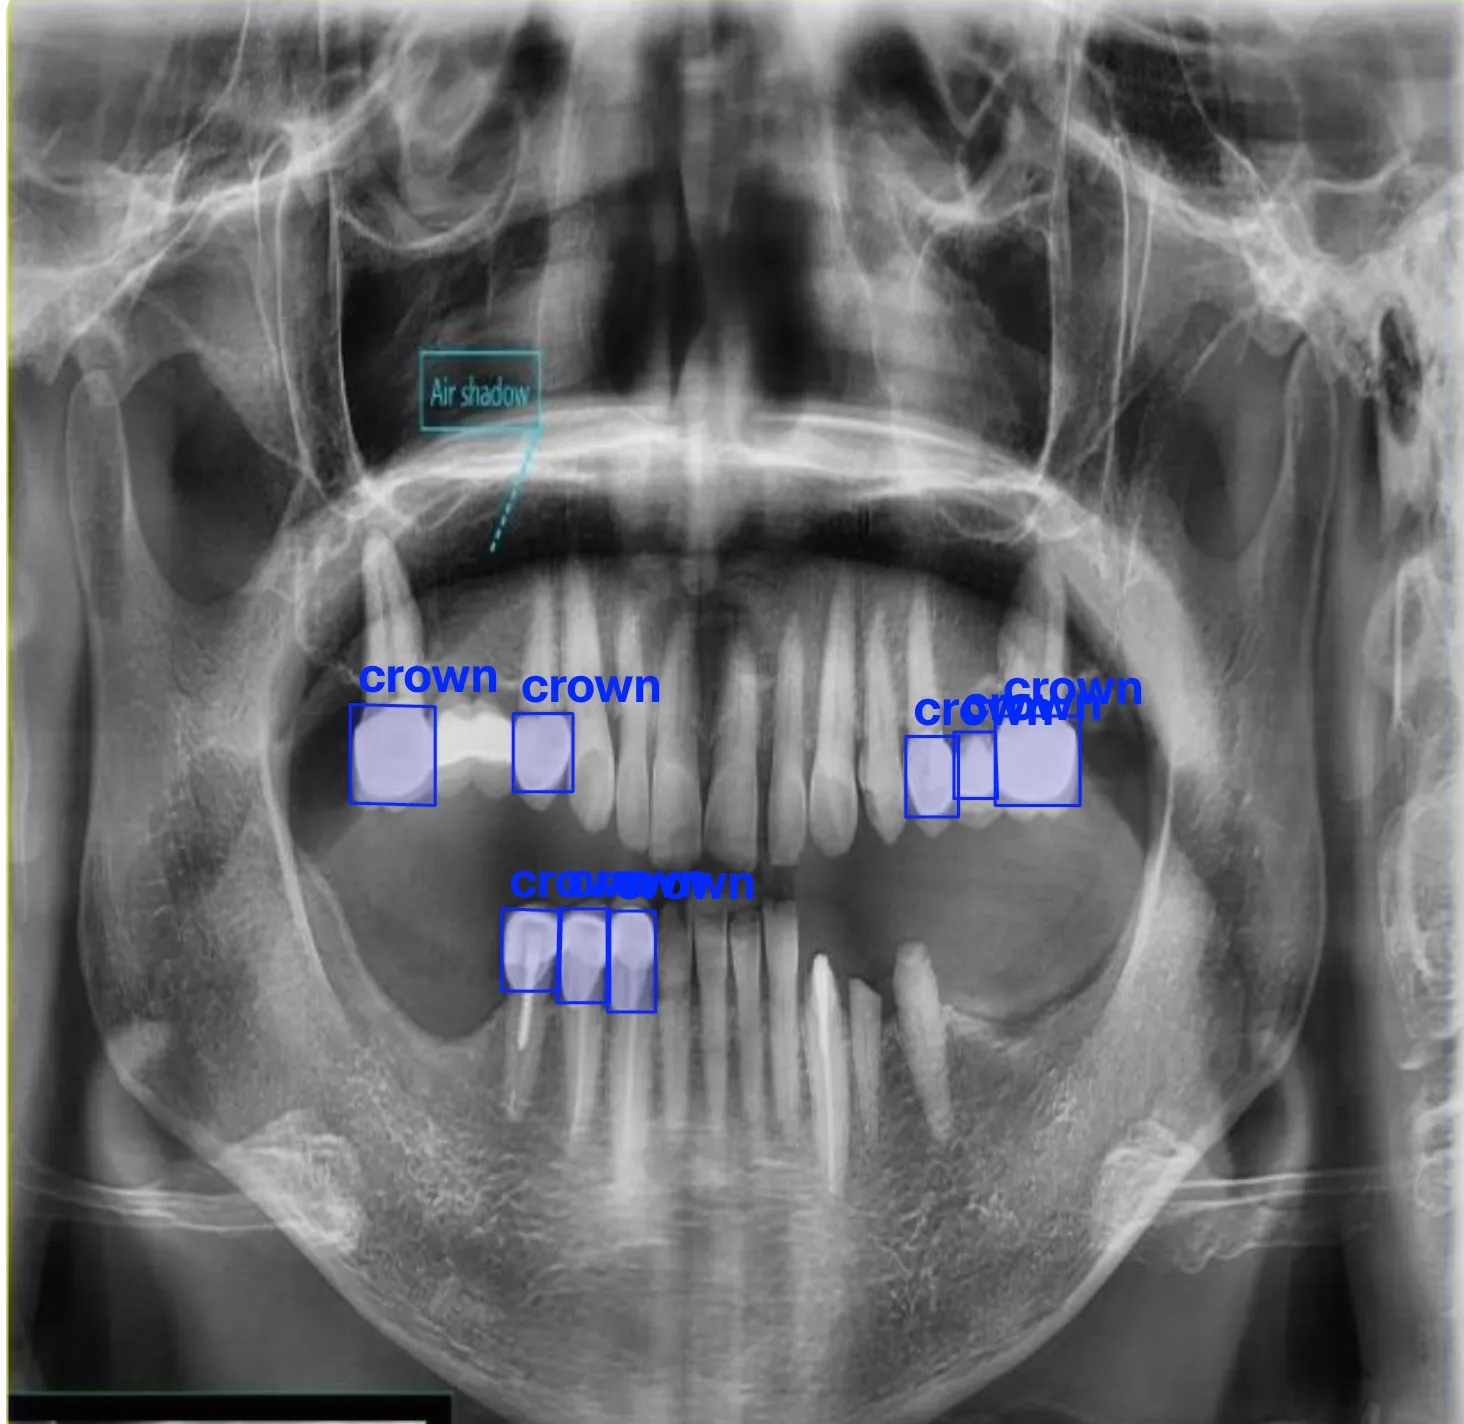

Building computer vision datasets and training YOLO models for automated dental pathology detection on panoramic X-rays.

- Crown and bridge work informing crown detection model

Annotating dental X-rays with clinician-grade precision for object detection and OBB tasks.

Training and publishing YOLO-based detection models for dental diagnostics on Ultralytics Hub.